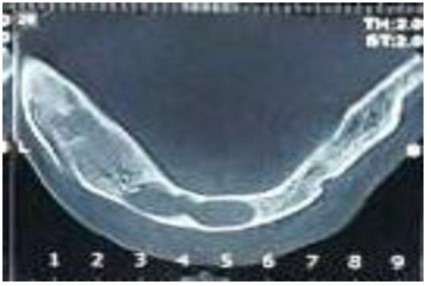

The panoramic radiographs showed seven cysts in the mandible and maxilla. The patient was then referred to the surgical unit of the School of Dentistry. A CT scan was performed in order to better examine the patient and the images obtained revealed multiple extended cysts in the posterior and anterior mandible and maxilla with no swelling. The CT scan and panoramic radiographs showed multiple radiolucencies with well-demarcated borders, cortical margins and different sizes (Figure 3 and Figure 4). The interpretation of the radiographic images diagnosed the patient with radicular cysts and odontogenic keratocysts. The clinical examination of the patient revealed no systemic diseases or symptoms in the skin and the involved areas. The chest and skull radiographs also showed no symptoms.

Figure 4.The axial cross-section of the CT scan showing radiolucencies with well-defined borders